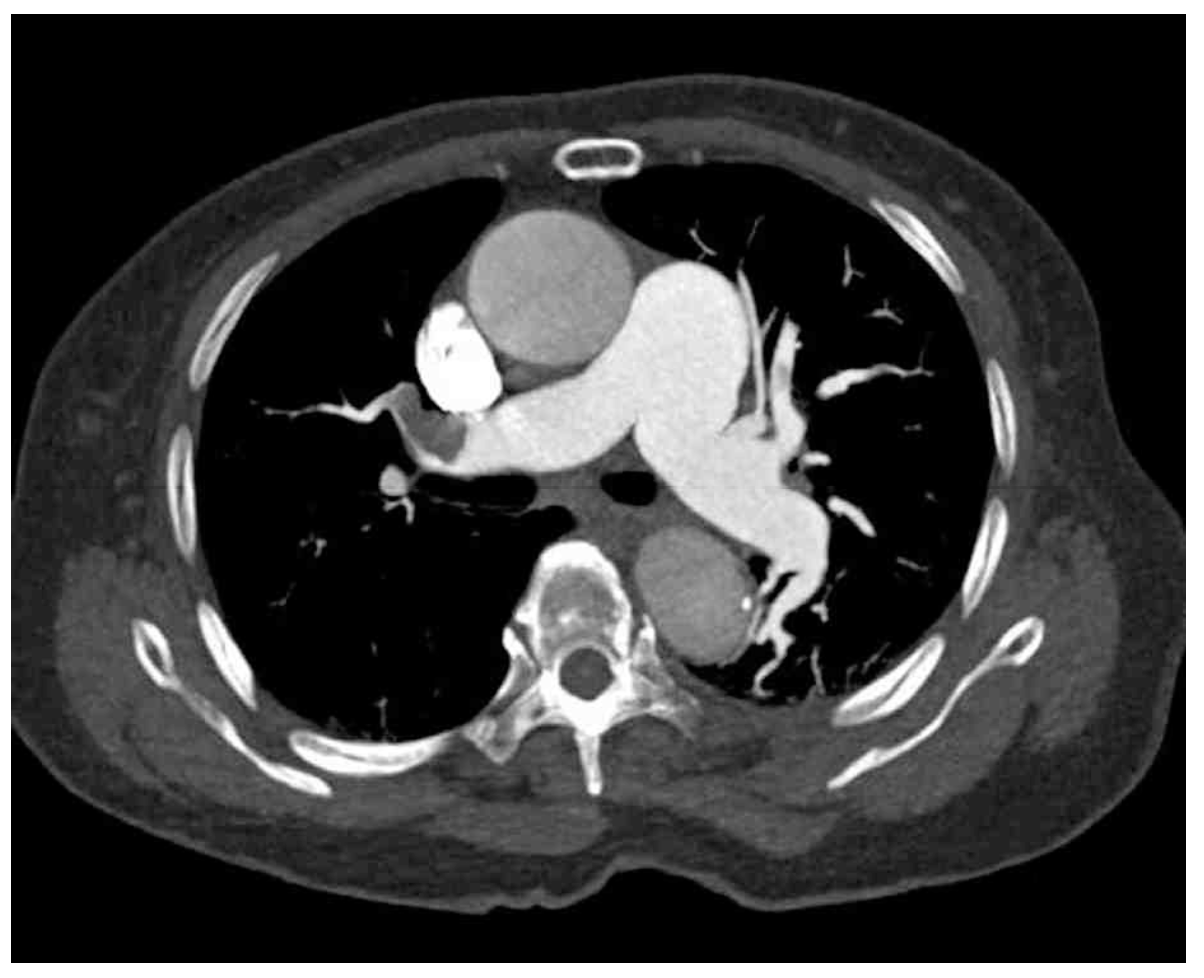

70세 여자가 직장암으로 저위전방절제를 받고 입원 중이다. 수술 후 2일째 가슴이 답답하다고 한다. 혈압 90/65 mmHg, 맥박 105/분, 호흡 28회/분, 체온 36.8°C이다. 양측 폐의 호흡음은 정상이며, 배는 수술부위 통증 외에 특별한 이상은 없다. 검사 결과는 다음과 같다. 가슴 X선사진과 가슴 컴퓨터단층촬영 사진이다. 진단은?

CT: Rt. pulmonary artery thrombosis

수술 후 급성 호흡곤란을 호소하는 환자에서 흉부 CT상 폐동맥 혈전이 확인되므로 폐색전증을 진단할 수 있다.

• 폐색전증의 확진은 가슴 컴퓨터단층촬영을 통해 진행하며, 우측 폐동맥혈전이 저명하게 관찰되므로 폐색전증을 진단할 수 있다.